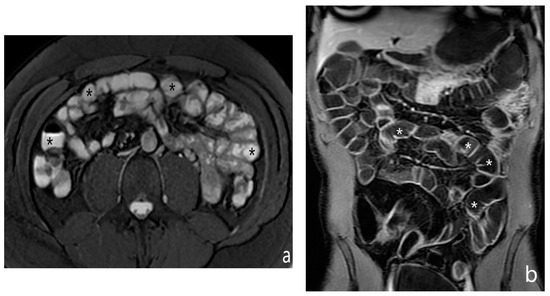

5.1. Active Subtype